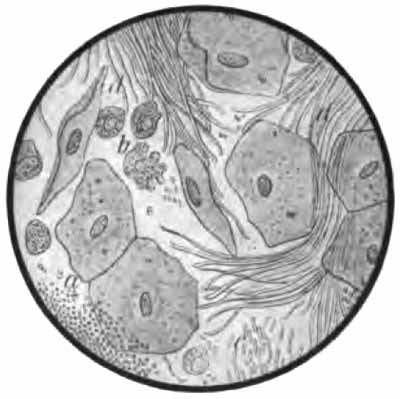

(2) Epithelial cells may come from any part of the [p. 42] respiratory tract. A few are always present. They have little diagnostic value, although a considerable excess would indicate a pathologic condition at the site of their origin. Any of the stains mentioned above will show them, and they can usually be identified in unstained sputum. In general three forms are found:

(a) Squamous cells: large, flat, polygonal cells with a comparatively small nucleus (Fig. 13, i). They come from the upper air-passages, and are especially numerous in laryngitis and pharyngitis. They are frequently studded with bacteria—most commonly diplococci.

| FIG. 13.—Different morphologic elements of the sputum (unstained): a, b, c, Pulmonary or alveolar epithelium—a, with normal lung pigment (carbon); b, with fat-droplets; c, with myelin globules; d, pus-corpuscles; e, red blood-corpuscles; f, cylindric beaker-shaped bronchial cells; g, free myelin globules; h, ciliated epithelium of different kinds from the nose, altered by coryza; i, squamous cells from the pharynx (after Bizzozero). |

(b) Cylindric cells from the nose, trachea, and bronchi (Fig. 13, f, h): These are not usually abundant, and, [p. 43] as a rule, they are not identified because much altered from their original form, being often spheric.

(c) Alveolar cells: rather large, round, or oval cells with one or two round nuclei (Fig. 13). Their source is presumably the pulmonary alveoli. Like the leukocytes, they frequently contain particles of carbon (normal lung pigment). In chronic heart disease, owing to long-continued passive congestion, they may be filled with brown granules of altered blood-pigment, and are then called "heart-failure cells" (Plate II, Fig. 1). Alveolar cells commonly contain fat-droplets and, less frequently, myelin globules. The latter are colorless, rounded bodies, sometimes resembling fat droplets, but often showing concentric or irregularly spiral markings (Fig. 13, c, g). They are also found free in the sputum. They are abundant in the scanty morning sputum of apparently healthy persons, but may be present in any mucoid sputum.